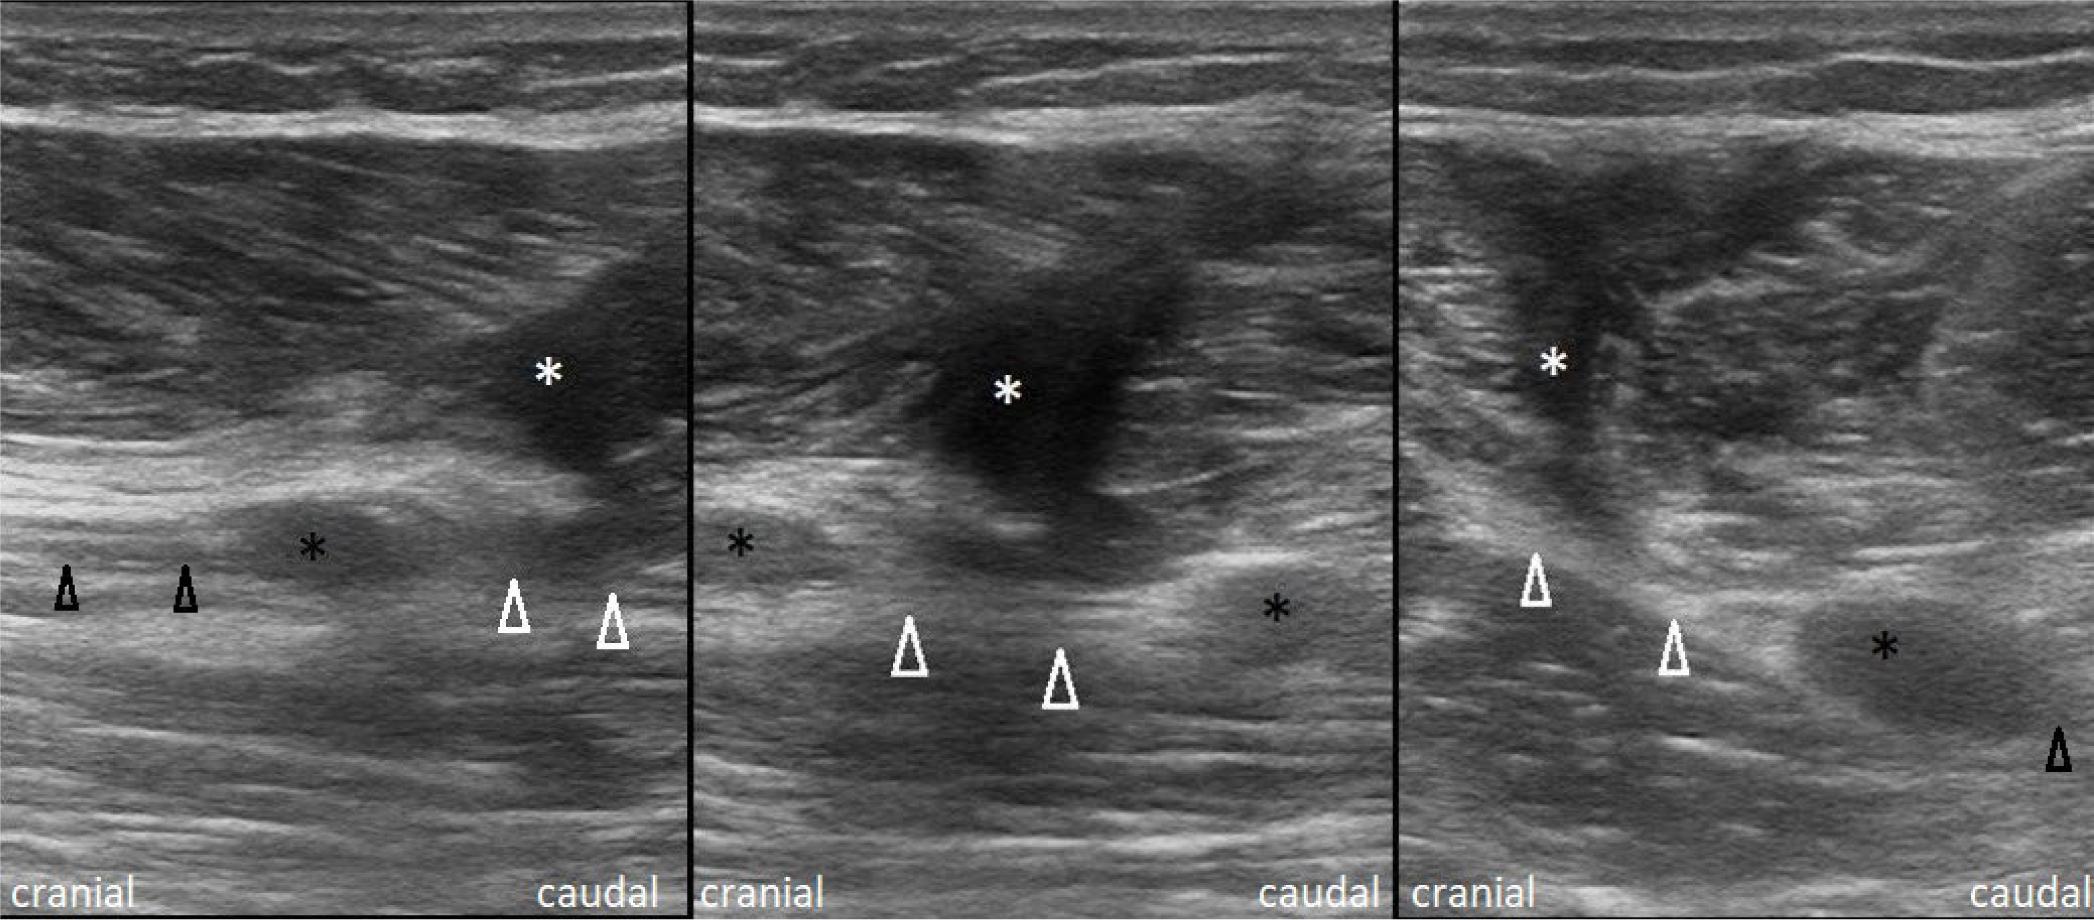

Fig. 1.